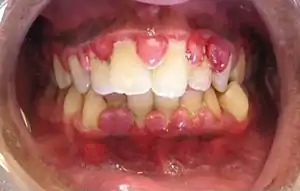

The symptoms of gingivitis are somewhat non-specific and manifest in the gum tissue as the classic signs of inflammation:

- Swollen gums

- Bright red or purple gums

- Gums that are tender or painful to the touch

- Bleeding gums or bleeding after brushing and/or flossing

- Bad breath (halitosis)

Additionally, the stippling that normally exists in the gum tissue of some individuals will often disappear and the gums may appear shiny when the gum tissue becomes swollen and stretched over the inflamed underlying connective tissue. The accumulation may also emit an unpleasant odor. When the gingiva are swollen, the epithelial lining of the gingival crevice becomes ulcerated and the gums will bleed more easily with even gentle brushing, and especially when flossing.